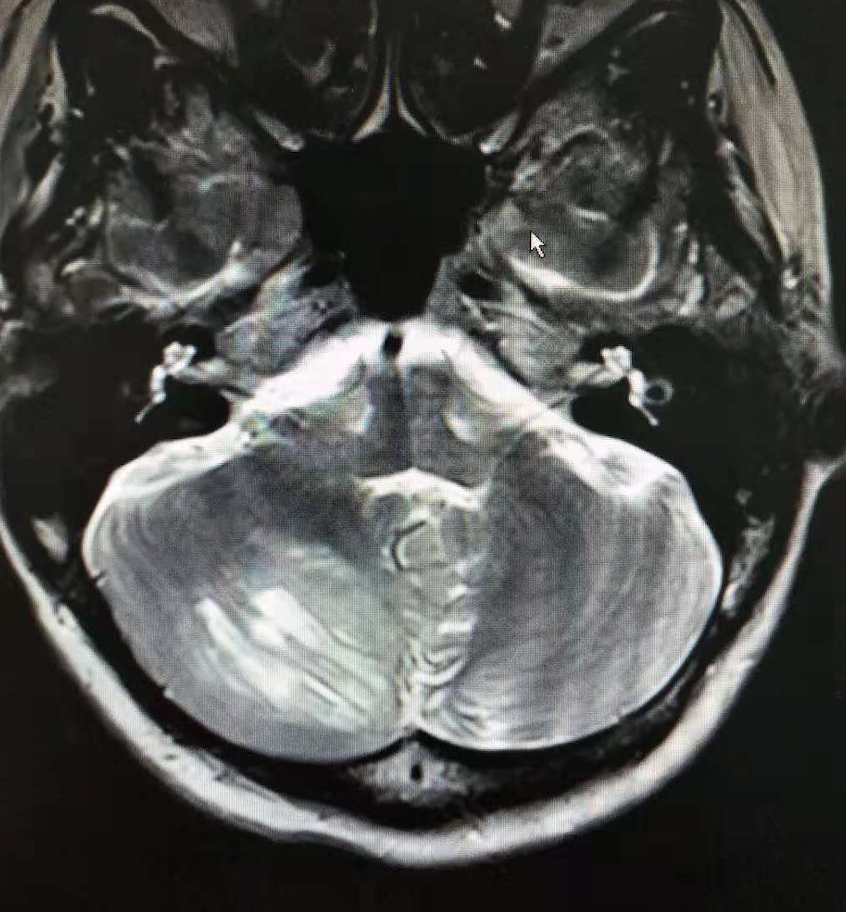

前段时间整理病例时,发现我们科曾经诊治一例罕见疾病。患者,女,38岁,因发现乳腺肿块就诊于某院,检查发现双侧乳腺多发占位,肝内多发占位。活检病理证实该患者为双侧乳腺浸润性导管癌并肝内多发转移,遂来我科就诊。我科完善相关检查,颅脑MRI检查显示:右侧小脑半球可见一类椭圆形肿块样异常信号区,呈分层状结构(虎纹征)。如图:

我们院影像科医生诊断为小脑发育不良性神经节细胞瘤(不得不说我们影像科医生的实力还是不容小觑的)。小脑发育不良性神经节细胞瘤(dysplastic gangliocytoma of cerebellum),最早是由Lhermitte和Duclos于1920年报道,故也称之为Lhermitte-Duclos病(Lhermitte-Duclos disease, LDD)。